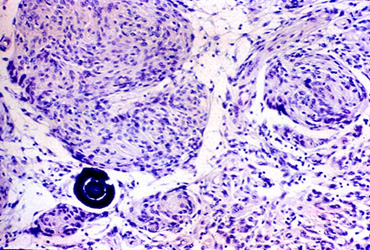

Question 19: Which of the following statements about the lesion shown below is not true?

Incorrect. The picture shows whorls of tumor cells and a psammoma body (meningioma). Most meningiomas are benign and do not invade the brain.

Correct. The picture shows whorls of tumor cells and a psammoma body (meningioma). Most meningiomas are benign and do not invade the brain.